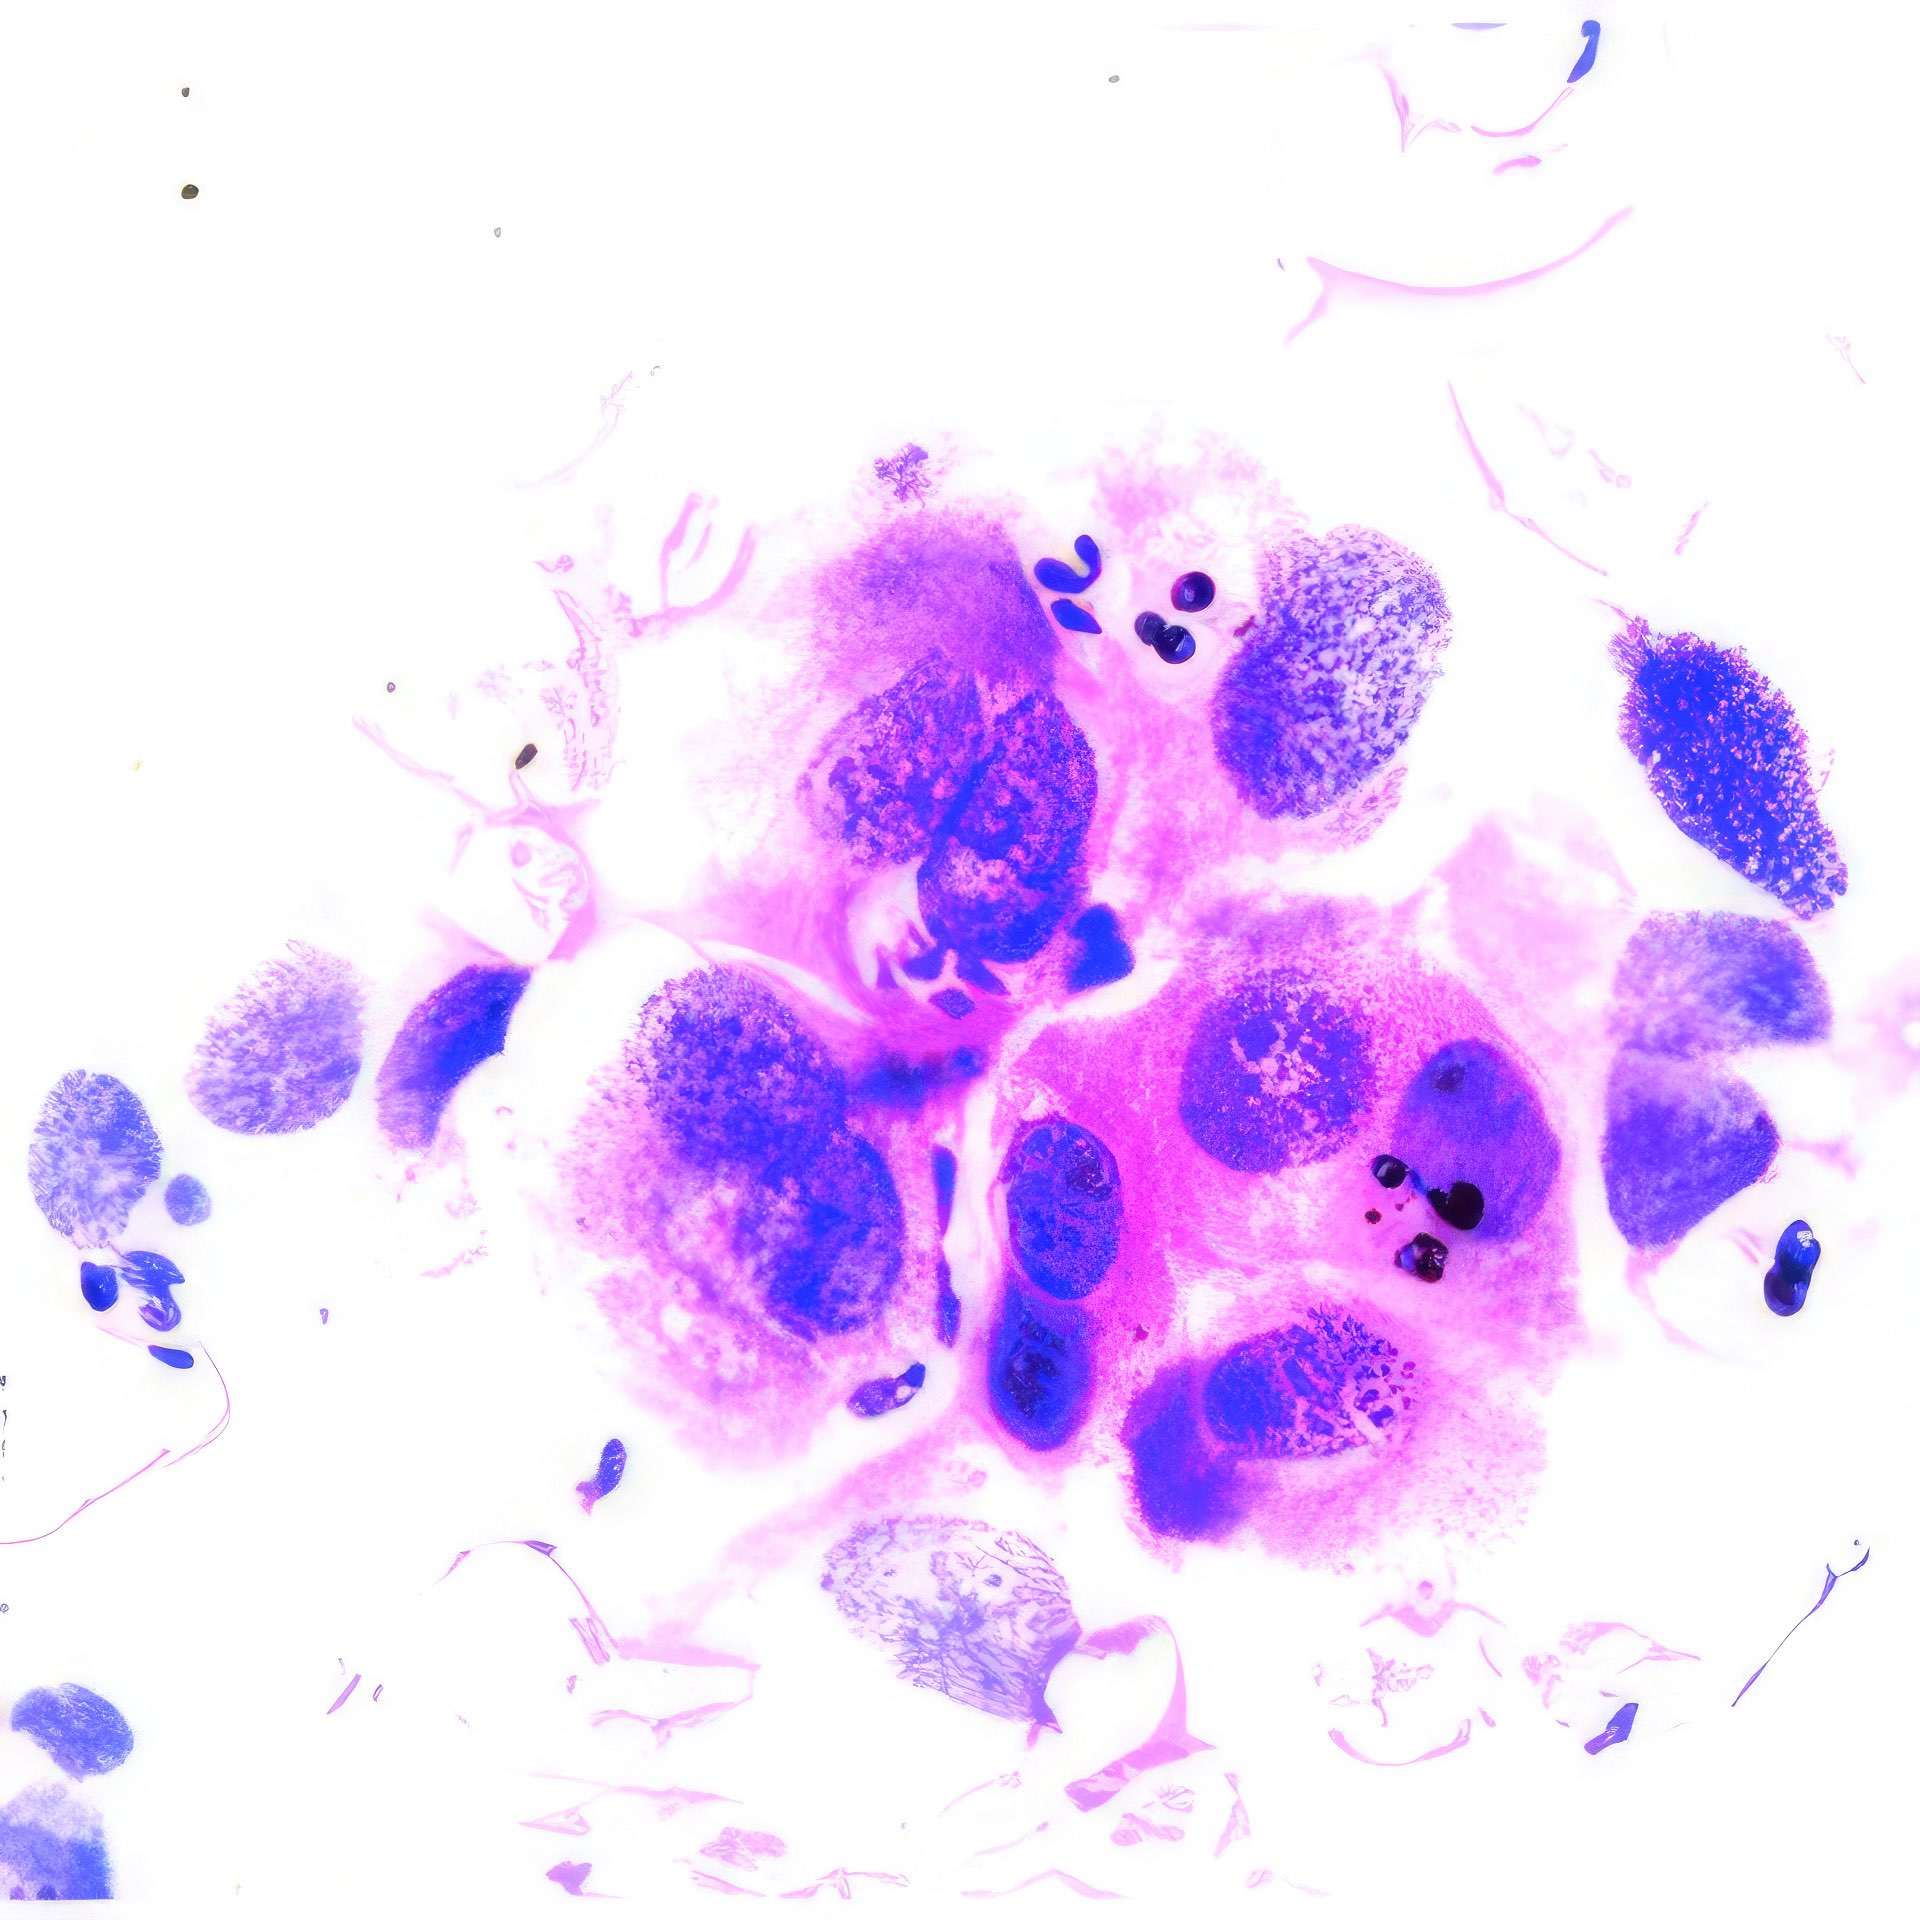

M, 55 Jahre, bemerkte seit 3 Monaten eine zunehmende inguinale Lymphknotenschwellung, der größte 3 x 4 cm messend, davon Feinnadelaspiration (FNA). Abbildung 1 bis 4: Verschiedene Areale des zytologischen Ausstrichs. Orig. 63x

Beschreibung

Die Bilder zeigen hochatypische Zellen. Deren überwiegend runde, teils auch ovalen Kerne variieren erheblich in ihrer Größe, sind deutlich grob strukturiert und enthalten meist ein oder mehrere prominente Nukleolen bzw. Chromozentren. Das Zytoplasma erscheint fragil. In jedem Bild finden sich auch Zellen mit pigmentbeladenem Zytoplasma. Der Ausstrichhintergrund enthält Blut und Zelldetritus, ebenfalls vermischt mit Pigmentkörnchen.

Kommentar

Der Patient beobachtete seit einem Jahr am Fuß eine pigmentierte Veränderung, die seit 3 Monaten auf 3 cm Durchmesser zunahm. Die prominente Atypie und die pigmenthaltigen Zellen sowie die ausgedehnte Metastasierung in die inguinalen Lymphknoten sind typisch für das Melanom. Eine Verwechslung des Melanin-Pigments mit Hämosiderin ist wegen der Zellatypie so gut wie ausgeschlossen. – Amelanotische Melanome zeigen oft eine weniger ausgeprägte Kernatypie und sind eher mit einem anderen Tumor zu verwechseln.